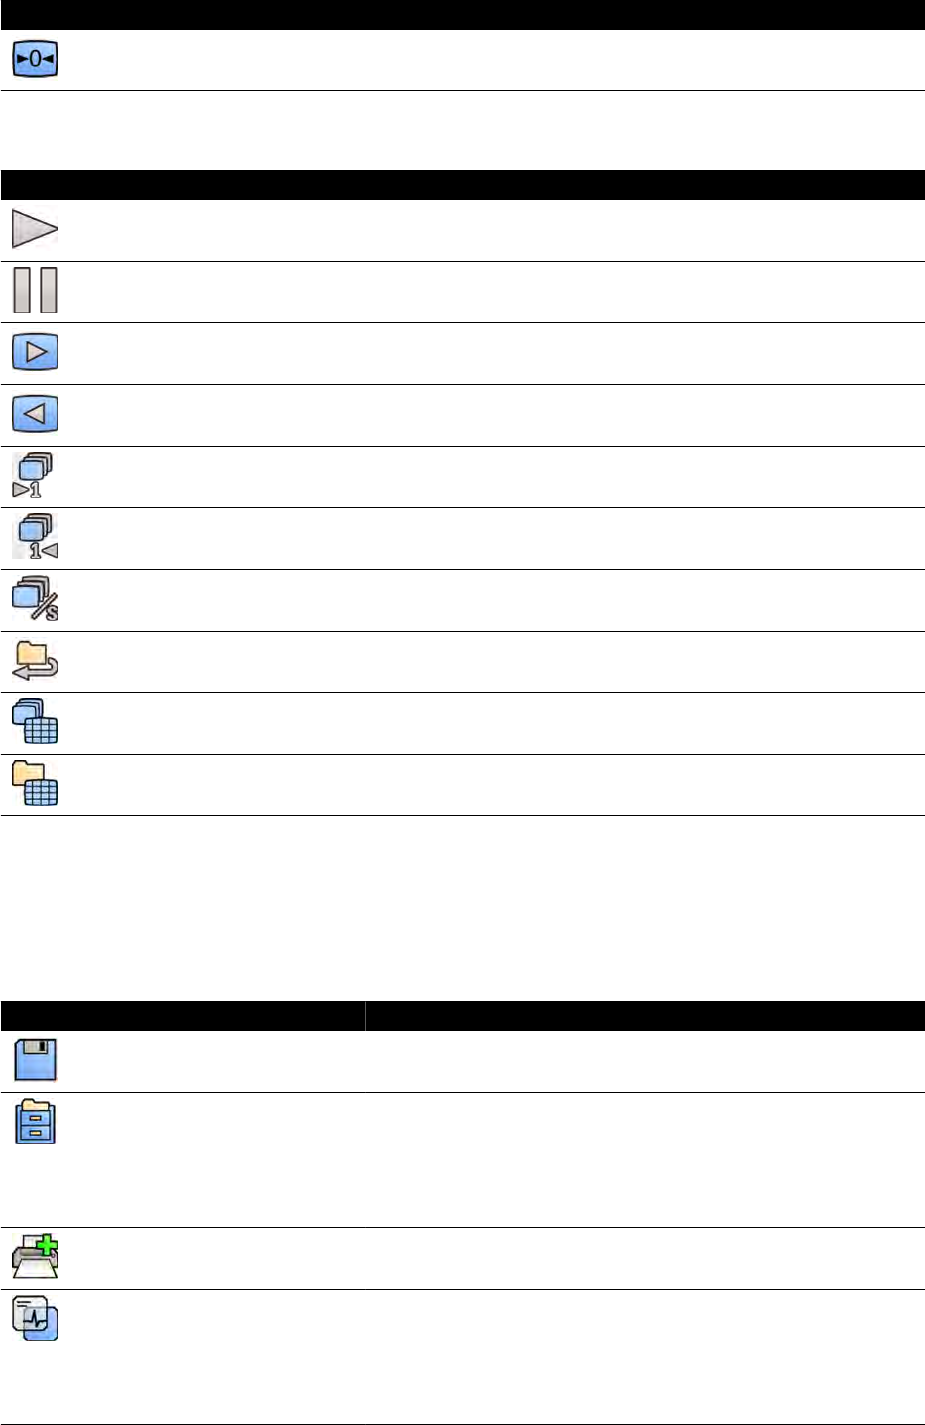

3.1.1 Ramię C.................................................................................................................. 26

3.1.3 FlexMove (opcja)....................................................................................................27

3.1.4 Zapobieganie kolizji (BodyGuard).......................................................................... 28